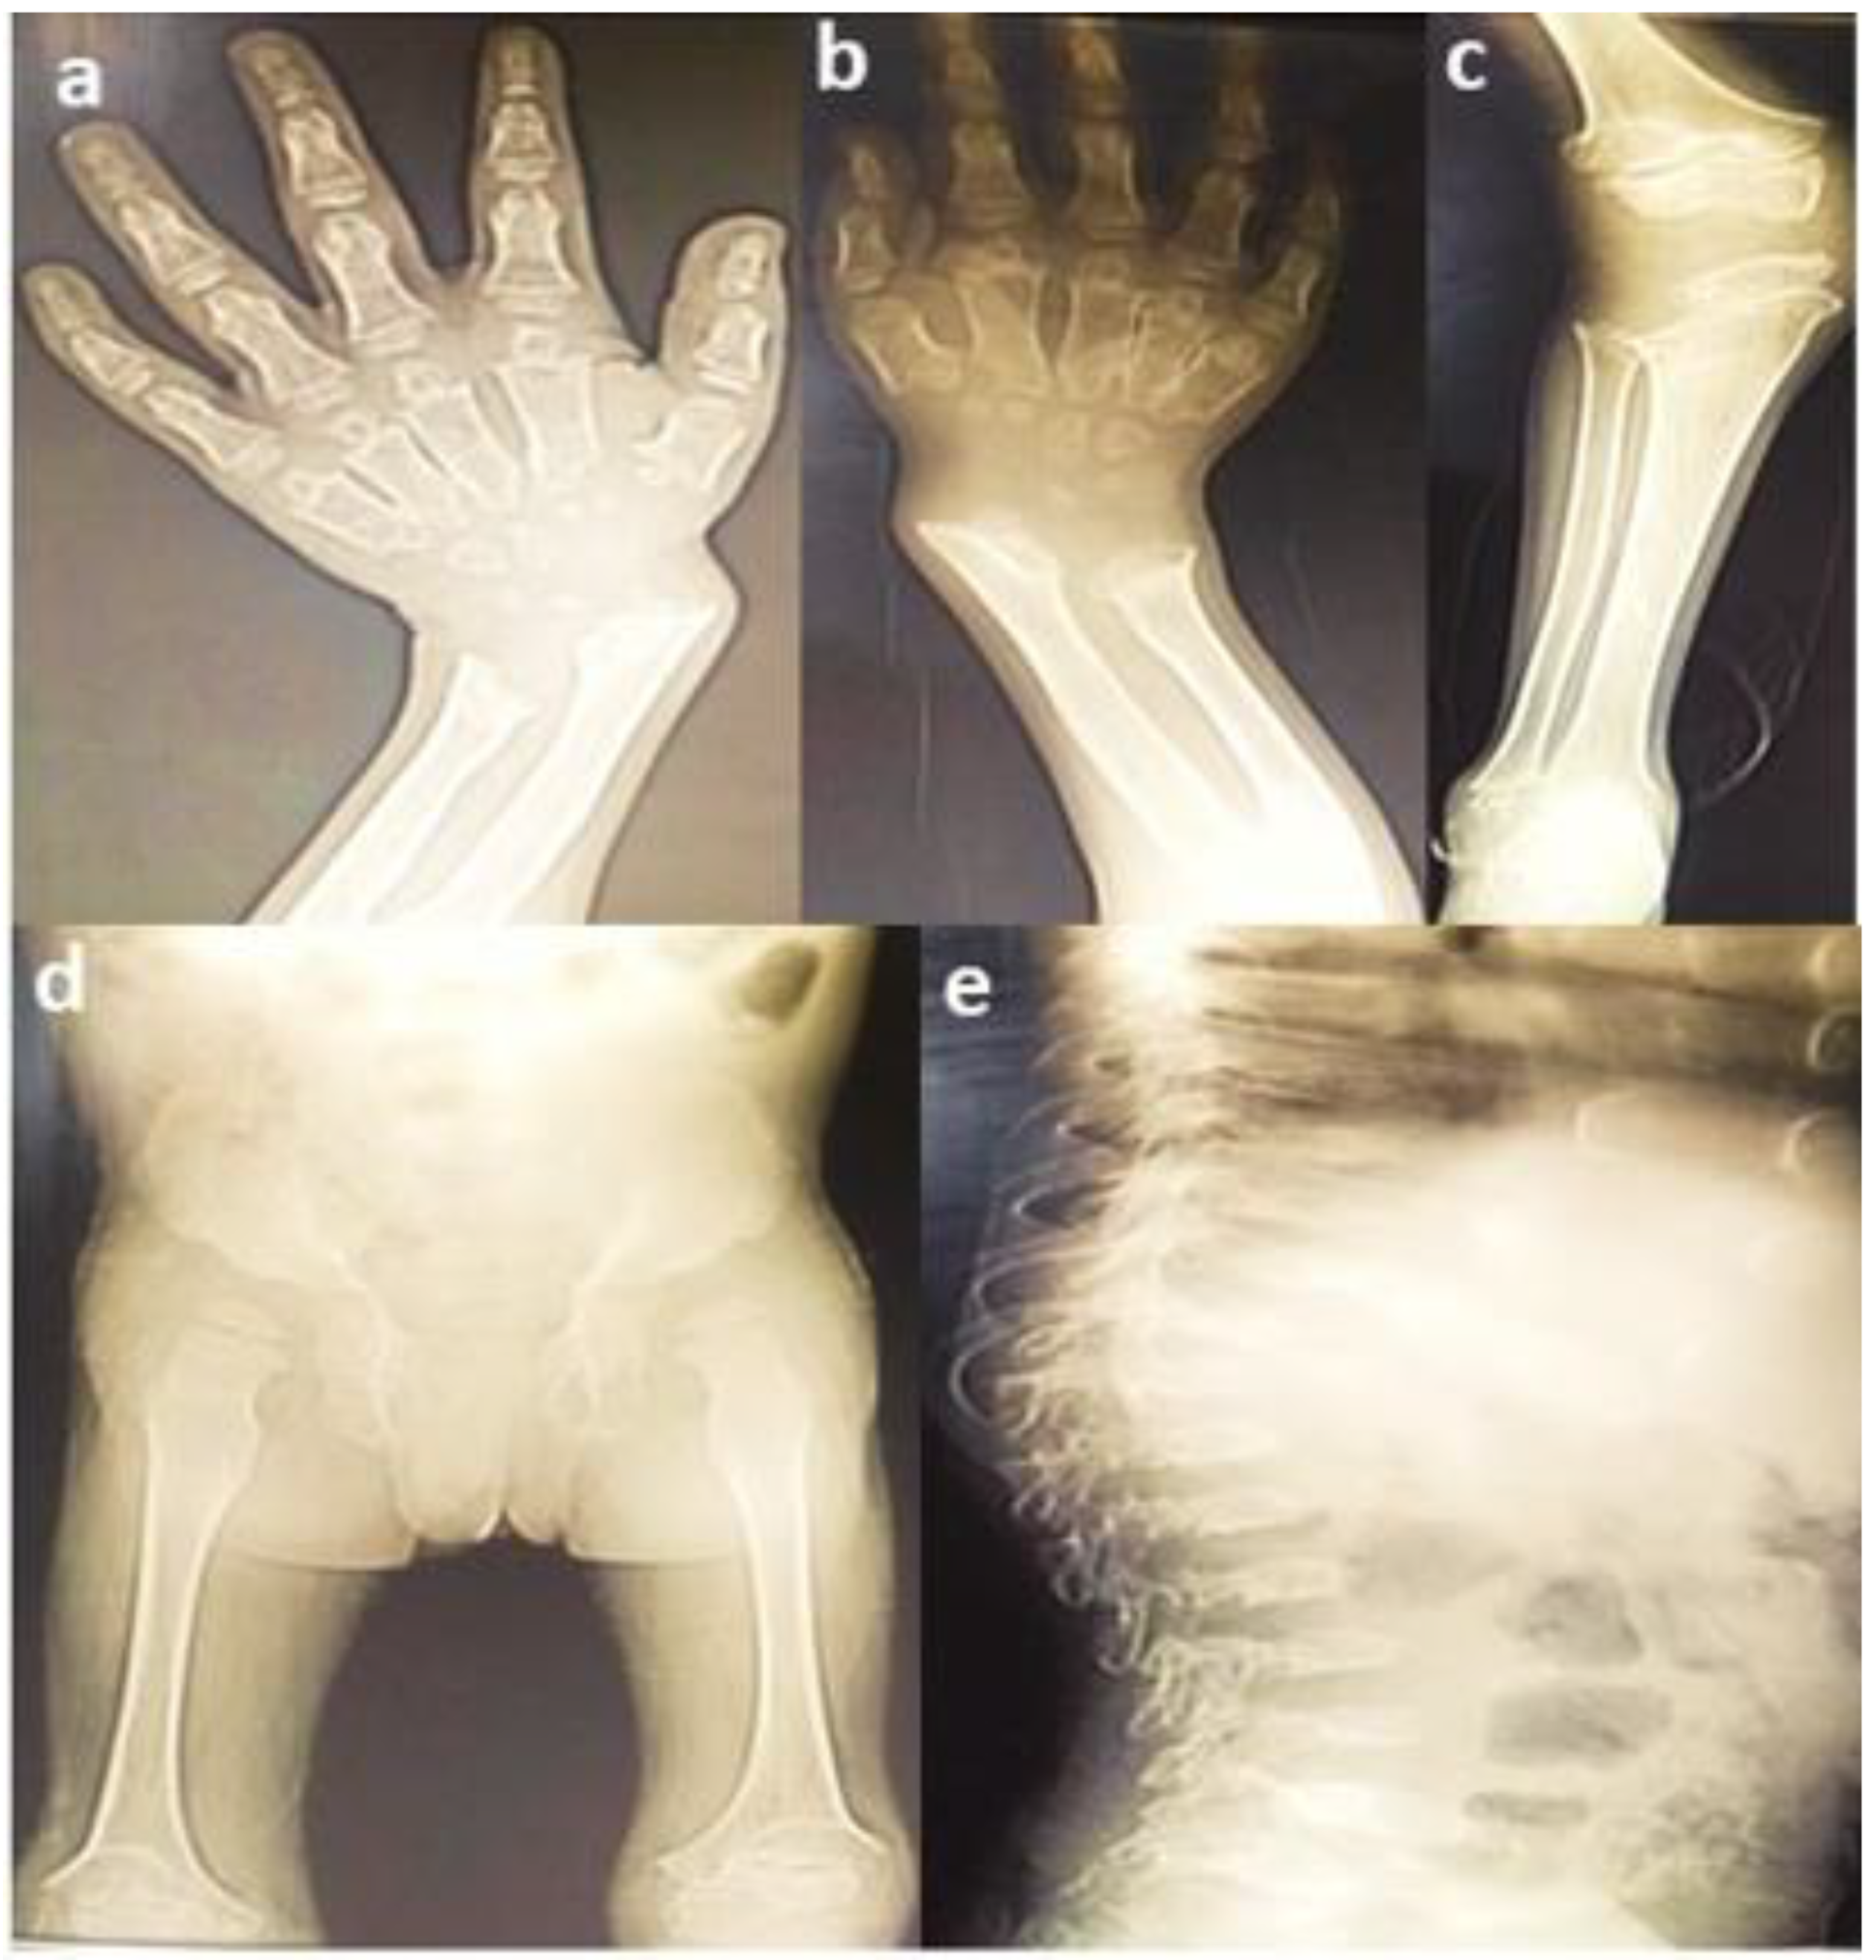

3.1. Clinical Findings

| Severe | Homozygous (p.Asp233Asn) | Spondylo-epiphyseal dysplasia, short stature, chest protrusion, short neck, vulgus deformity of the knees, scoliosis, and, abnormal gait | 7 | GG = 2 AA = 4 GA = 3 | 16.6% 33.3% 50% | 0.00001 | Familial | Pakistani | Current study |